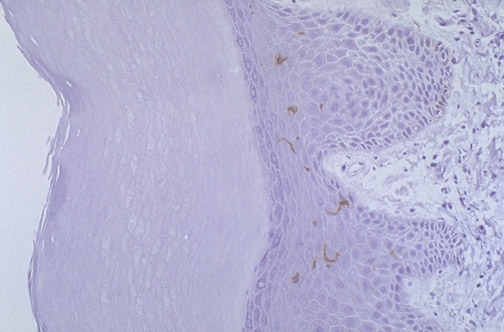

| The long processes of a form of dendritic cell known as a Langerhans cell are seen here with antibody to CD-1 in this section of skin viewed at medium power. Dendritic cells function as the "goalkeepers" of the immune system, reaching out their long arms (processes) to capture antigens to present to lymphocytes. Langerhans cells are present in skin and mucosal surfaces. |